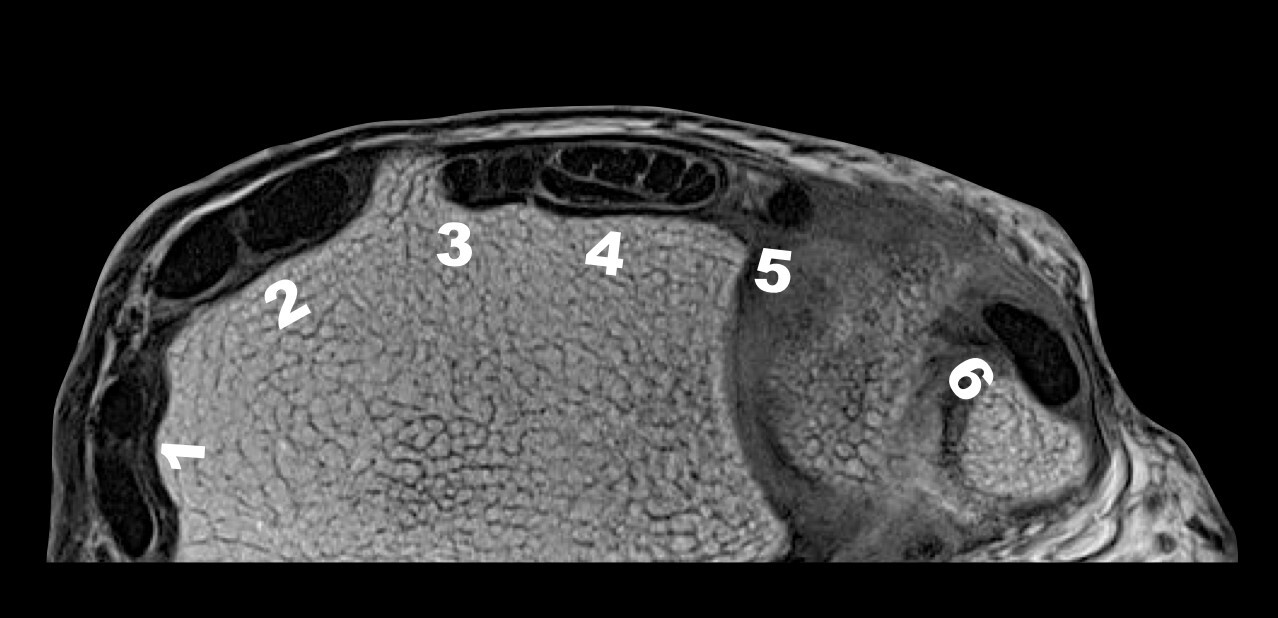

Wrist Compartments MRI Image

1. Abductor Pollicis Longus and Extensor Pollicis Brevis (Compartment 1)

2. Extensor Carpi Radialis Longus and Extensor Carpi Radialis Brevis (Compartment 2)

Lister’s tubercle is in between compartment 2 and compartment 3

1. Extensor Pollicis Longus (Compartment 3)

2. Extensor Digitorum and Indicis (Compartment 4)

The radial ulnar joint rests in between compartment 4 and compartment 5

1. Extensor Digiti Minimi (Compartment 5)

2. Extensor Carpi Ulnaris (Compartment 6) (over the ulnar styloid)